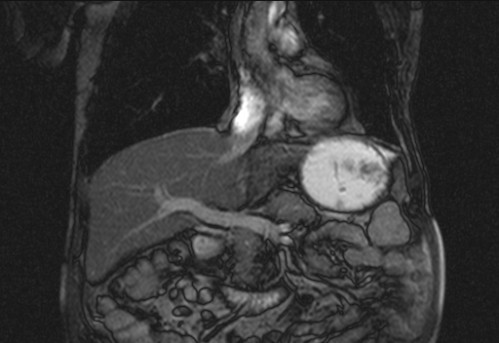

Auffälliges Abdomen bei der Vorsorgeuntersuchung einer älteren Dame

ICD: C64

68 Jahre alte Frau. Sie geht zur Darmspiegelung im Rahmen ihrer Krebsvorsorgeuntersuchung. Der Internist bemerkt bei der ergänzenden sonografischen Untersuchung des Abdomens einen auffälligen Befund.